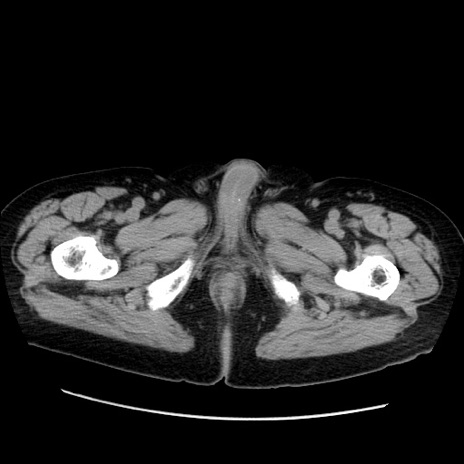

症例21(横断像)

【症例】70歳代男性

【主訴】腹痛

【現病歴】肝硬変・肝細胞癌にてかかりつけの方。約9時間前に食後より腹痛出現。症状が徐々に増悪し、嘔吐出現したため来院。

【既往歴】肝硬変、肝細胞癌(RFA、TACE後)

【身体所見】意識清明、表情苦悶様、BT 36℃、BP 129/78mmHg、P 88bpm、SpO2 97%(RA)、右上腹部から心窩部にかけて圧痛あり、反跳痛なし、筋性防御あり。

【データ】WBC 5800、CRP 0.16